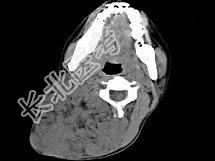

- 单项选择题女,32岁, 颈部包块8年余,包块逐渐长大, CT如图所示,最可能的诊断为 ( )

A、颈部神经纤维瘤

B、颈部横纹肌肉瘤

C、颈部巨大血管瘤

D、颈部神经鞘瘤

E、颈部异位甲状腺